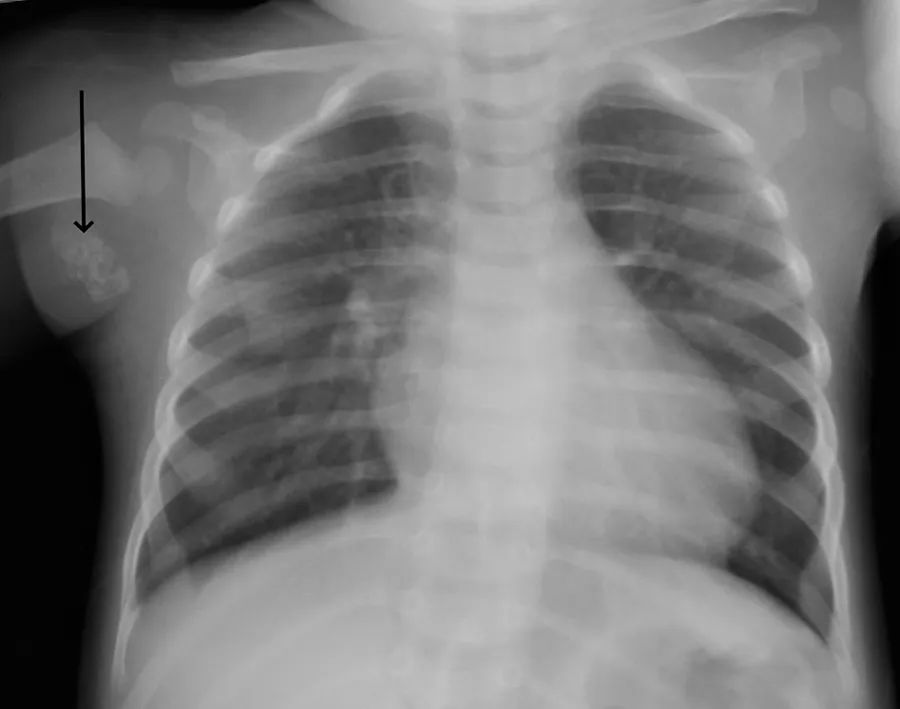

2月龄时,曾因咳嗽、发热做过X线胸片。后经过对症治疗,痊愈。

X线胸片,腋下钙化灶。

答案卡介苗接种反应(腋淋巴结钙化)